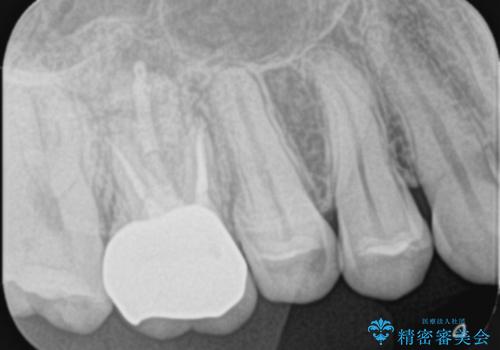

- 他院で歯の根っこの先端に膿が溜まっているため治療が必要だといわれた患者様です。

根っこの治療を顕微鏡を見ながら行ってくれる医院を探して当院に来院されました。

もともと症状はない状態でしたが、治療後は少しずつ病変の大きさが小さくなっているのを確認できます。

以前治療した際のむし歯が大きく、長い年月の間に少しずつ歯髄が死んでしまったと思われる状況でした。

長期にわたる炎症により、口蓋根尖は吸収を起こしていたため、MTAにて充填しています。